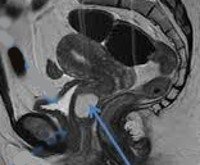

• Ультразвуковое исследование. Трансвагинальное УЗИ является оптимальным с точки зрения точности, надежности и доступности среди инструментальных методов диагностики объемных образований. Ультразвуковые признаки кисты включают четкие контуры, однородное гипоэхогенное содержимое полости, отсутствие связи с уретрой.